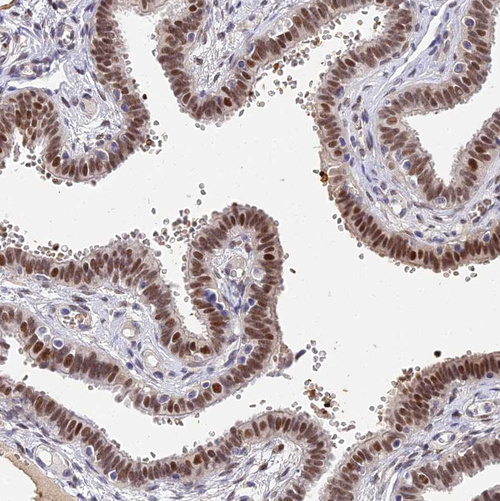

Immunohistochemistry analysis in human fallopian tube and pancreas tissues using HPA020274 antibody. Corresponding BCL9 RNA-seq data are presented for the same tissues.